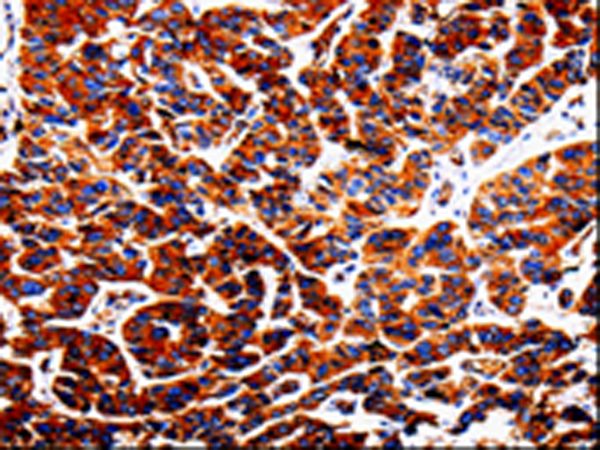

分类: 科研抗体货号: P06988别名: BCL2L4应用: WB,IHC反应种属: Human, Mouse, Rat